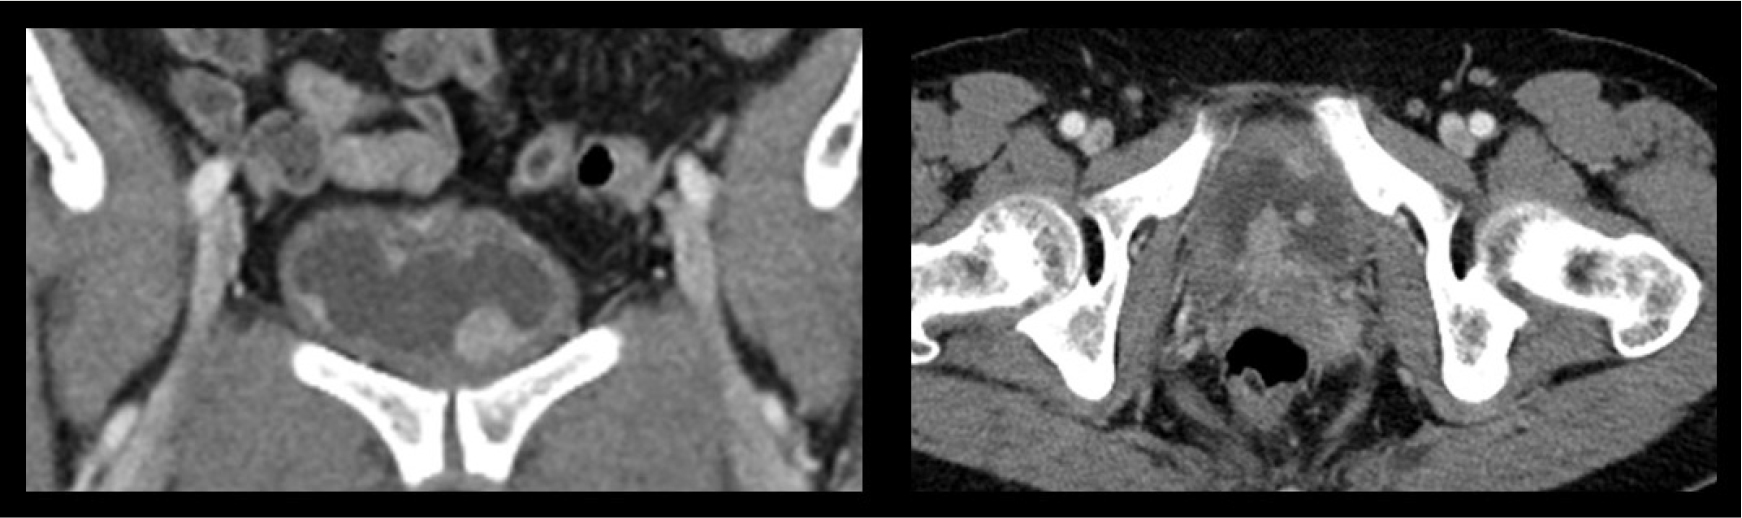

2.5. 복부 및 흉부 CT

전산화 단층촬영에서 방광벽에 여러 개의 조영 증강이 있는 결절이 있었다. 결절이 있는 부분의조영이 증강되었으며, 이 병변 주위는 다소 국소적으로 두꺼워져 있었다. 방광암이 의심되는 소견이며 복강내 비정상 임프절 비대 및 체액저류(fluid collection)은 없었다. 흉부CT에서 좌하엽(left lower lobe)의 posterior basal segment에 약 9 mm 크기의 폐결절(pulmonary nodule)이 관찰되었다.